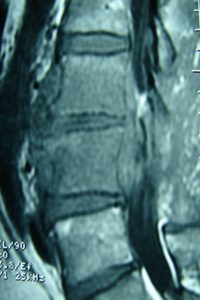

Μαγνητική Τομογραφία-Ακολουθία Τ1 και Τ2 της Ο.Μ.Σ.Σ. γενόμενη προ της εισαγωγής του στις 04/06/2007.

Οβελιαία τομή (α,β). Καταδεικνύεται η εκφύλιση του μεσοσπονδύλιου δίσκου στα επίπεδα Ο3-Ο4, Ο4-Ο5 και Ο5-Ι1 με μικρή οπίσθια προβολή ιδιαίτερα στο επίπεδο Ο3-Ο4. Ωστόσο στο επίπεδο αυτό είναι εμφανής η πρόσθια αποστηματική συλλογή.

Μετωπιαία τομή (γ,δ) Δεν είναι εμφανής η ύπαρξη της αποστηματικής συλλογής ωστόσο στο επίπεδο Ο3-Ο4 (Α) πιθανολογείται η ύπαρξη μάζας η οποία προκαλεί απώθηση του υοϊτού μυός.

Εγκάρσια τομή (ε,ζ) Είναι σαφής η ύπαρξη προ και παρασπονδυλικής αποστηματικής συλλογής και σε μικρότερο βαθμό οπισθίως εντός του σπονδυλικού σωλήνα.